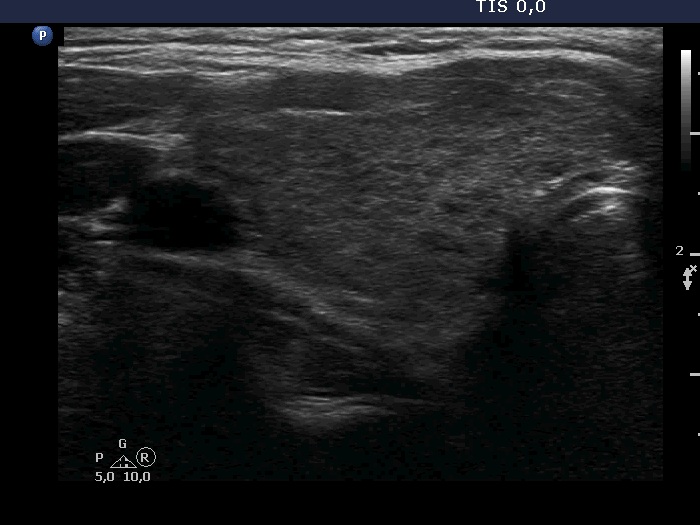

Ultrasonography. The thyroid was minimally hypoechoic and had more hypoechoic areas. There was a more hypoechoic nodule in the lower pole of the right lobe. The lesion has irregular, lobulated margins and numerous microcalcifications. A few microcalcification were found outside the core of the tumor. The intranodular vascularization was irregularly increased.

The ultrasound presentation of the nodule is very suspicious for papillary cancer. Indeed, this pattern is almost diagnostic.